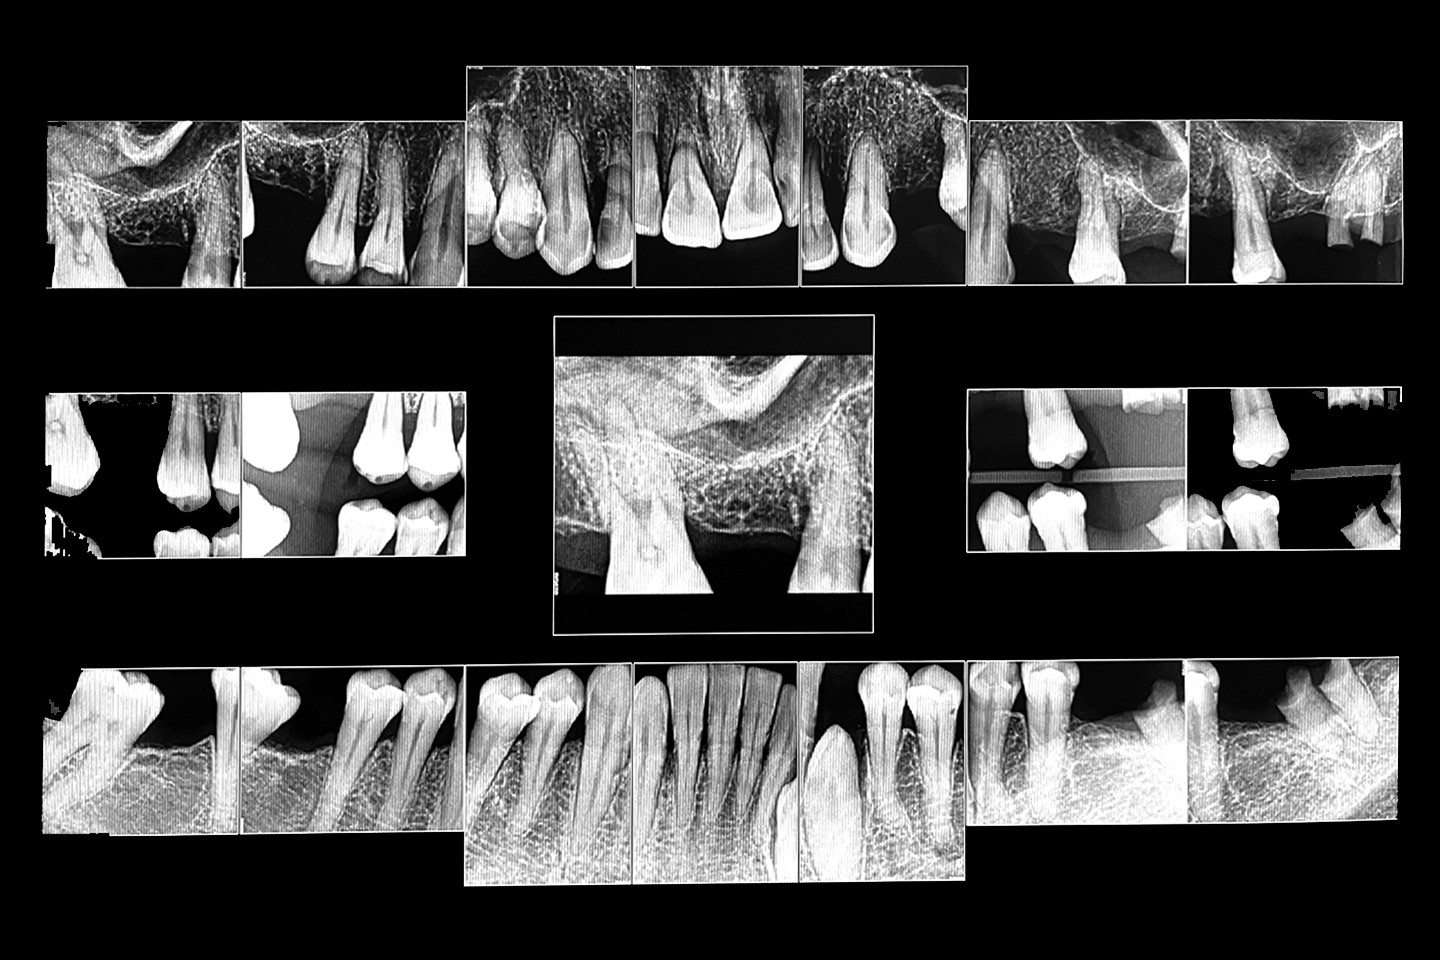

The following case exhibits the features and benefits of utilising Grammetry in combination with innovative screw technology. The 63-year-old male patient with a non-contributory medical history presented with failing dentition in both arches. Diagnostic records were collected, including full-mouth digital radiographs (RVG 6200, Carestream Dental; Fig. 11a), intra-oral scans (Medit i700 wireless; Figs. 11b & c), a large field of view CBCT scan (Carestream 9600; Fig. 11d), and intra-oral and extra-oral photographs (Fig. 11e). The mandible contained an impacted canine as well as several mobile and painful teeth. The maxilla was in a similar condition, having deteriorating, painfully mobile teeth, as well as extensive caries. While the bone loss was significant in the mandible, the vertical dimension of occlusion (VDO) allowed for both arches to be treated with an FP-1 prosthesis.

Fig. 11a: Full-mouth radiograph series revealing caries and periodontal defects.